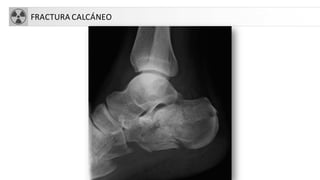

• Calcáneo

• Fx más frecuente del tarso y 2% del total.

• 75% intraarticulares.

• Mecanismo: caida de talones.

• Rx: disminuciónángulo de Böhler (normal 25-40º).

FRACTURA CALCÁNEO